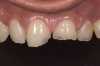

Figure 4  Preoperative smile view.

Figure 4

A 20-year-old male patient presented with irregular upper anterior teeth and was unhappy with his smile (Figure 4). He complained of occasional generalized mild sensitivity. Dental treatment history revealed that he had occasional dental work done in the past. Two weeks previously, he had severe pain in tooth No. 10, which was treated endodontically, and he was then referred to the author’s practice for management of anterior wear. Tooth No. 3 had a broken amalgam restoration.